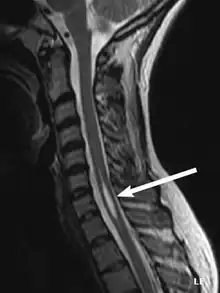

| An idiopathic syrinx | |

Physicians now use magnetic resonance imaging (MRI) to diagnose syringomyelia. The MRI radiographer takes images of body anatomy, such as the brain and spinal cord, in vivid detail. This test will show the syrinx in the spine or any other conditions, such as the presence of a tumor. MRI is safe, painless, and informative and has greatly improved the diagnosis of syringomyelia.[19]